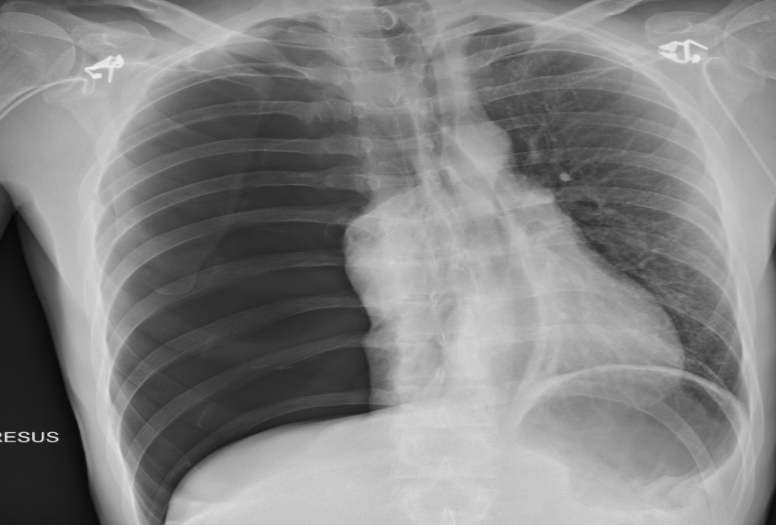

PA chest X-ray

Opacity on right side

Miniscus sign (indicates pleural effusion in PA view)

AP chest X-ray

Grading sign (indicates pleural effusion in AP view)